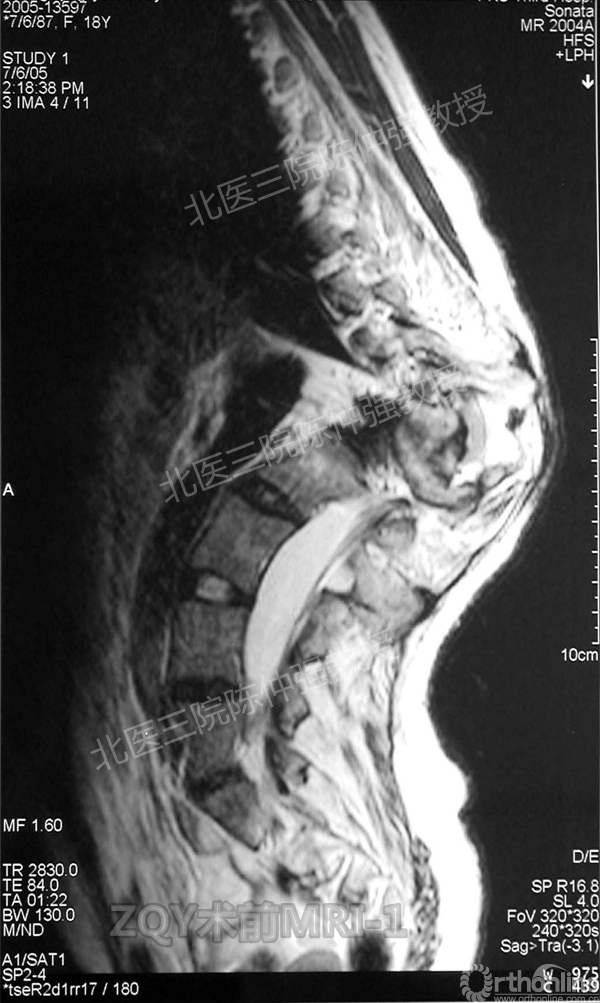

2005年,陈仲强教授在AOSpine年会上分享了一例胸腰椎陈旧结核性侧后凸畸形病例。资料如下:

ZQY术前

患者女性17岁,胸腰椎陈旧结核性侧后凸畸形,局部呈“麻花状”扭转,无神经功能受损表现。2005年,陈仲强教授带领团队实施后路+侧前方联合入路脊柱节段切除、双轴旋转矫形术。术后患者外观显著改善,神经功能正常。术后随访证实患者截骨矫形节段骨性融合良好,矫形效果持续良好。